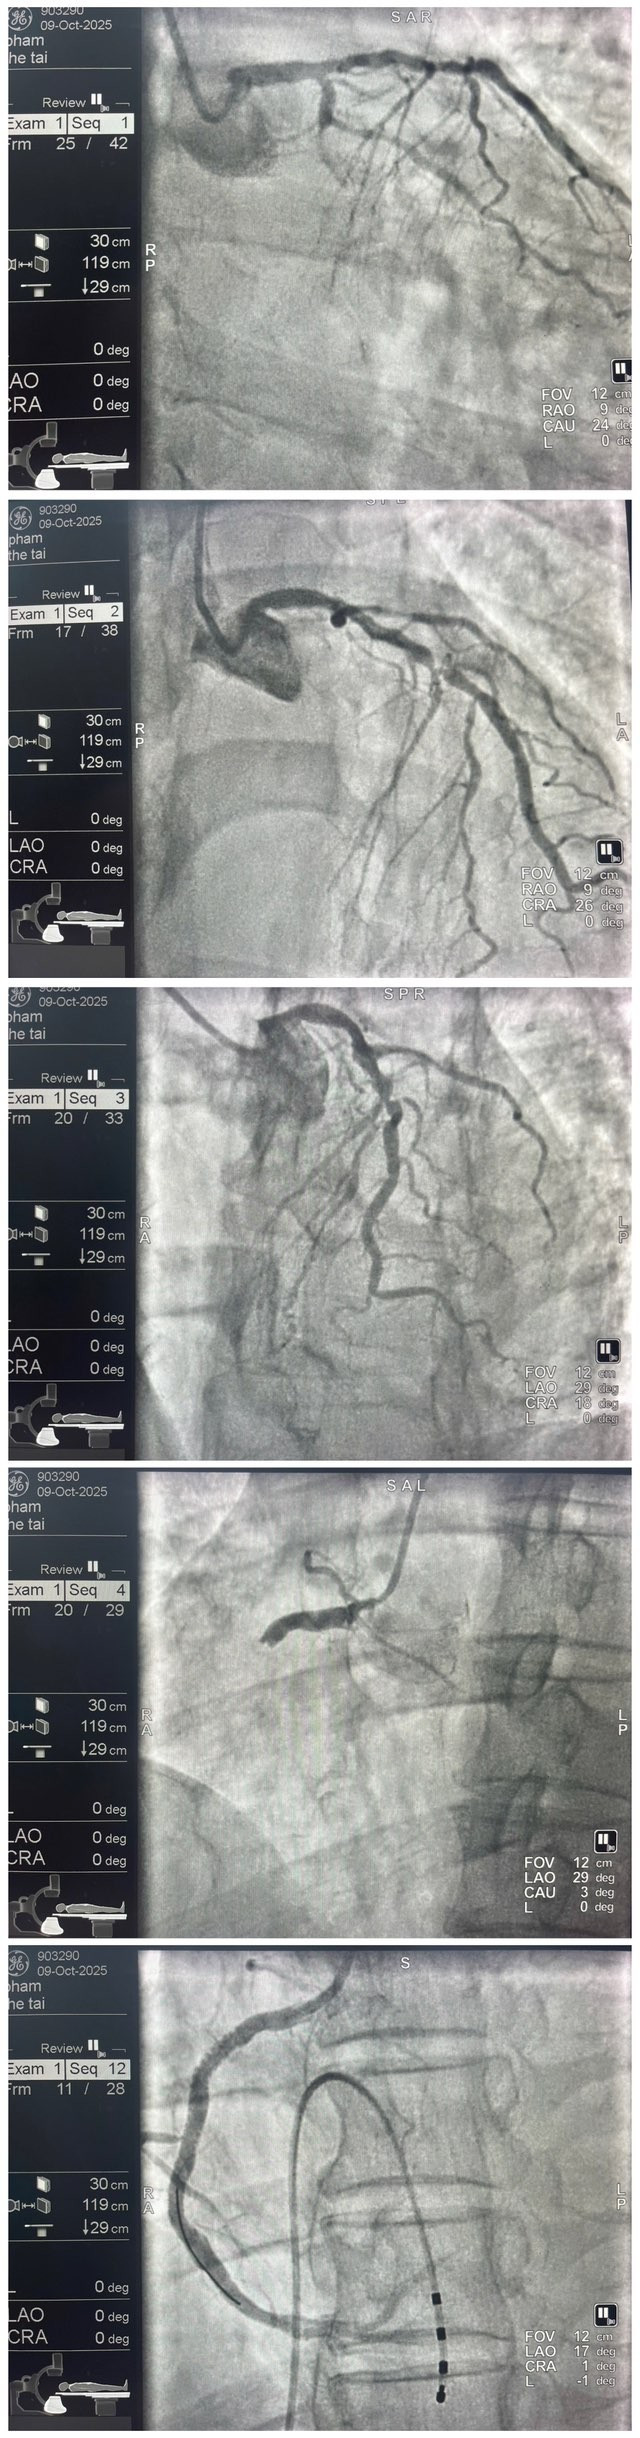

Kết quả điện tim cho thấy đoạn ST chênh lên ở các chuyển đạo DII, DIII, aVF — dấu hiệu điển hình của nhồi máu cơ tim cấp thành dưới (STEMI). Ngay lập tức, bệnh nhân được chỉ định chụp mạch vành cấp cứu.

Tại phòng can thiệp, kết quả chụp mạch cho thấy bệnh nhân bị tắc hoàn toàn động mạch mũ (Cx), tắc hoàn toàn động mạch vành phải (RCA) và hẹp nặng động mạch liên thất trước (LAD).

Ngay sau khi chụp mạch vành, bệnh nhân xuất hiện rung thất và rối loạn nhịp tim liên tục. Ê-kíp can thiệp đã kịp thời sốc điện chuyển nhịp, đặt nội khí quản, thở máy và sử dụng ba loại thuốc vận mạch gồm adrenaline, noradrenaline và dobutamine để duy trì huyết động ổn định.

Sau khi kiểm soát được tình trạng nguy kịch, các bác sĩ tiếp tục tiến hành can thiệp động mạch vành phải, lấy huyết khối, nong bóng và đặt stent tái thông mạch, giúp dòng máu được lưu thông trở lại bình thường.